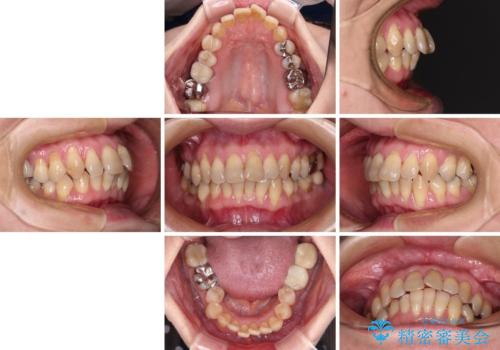

- 上下前歯のデコボコと、奥歯の銀歯を気にして来院された患者様です。

仕事柄あまり目立つ装置は付けることは避けたいとのことで、インビザラインによるマウスピース矯正を行うこととしました。

概ね歯列が整ったところで銀歯の全てをセラミッククラウンなどに置き換え、その後インビザラインを1セット使用して仕上げていくこととしました。